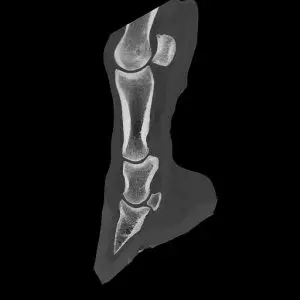

Die Computertomographie ist, ähnlich wie die Magnetresonanztomographie, ein Schnittbildverfahren. Anders als bei der MRT entstehen die CT-Bilder mit Hilfe von Röntgenstrahlen. Dabei wird das Pferd schichtweise durchleuchtet, und aus den zahlreichen Einzelaufnahmen errechnet ein Computer ein dreidimensionales Bild der untersuchten Region. So lassen sich selbst sehr kleine Veränderungen an Knochen oder Weichteilen sichtbar machen, die mit klassischen Röntgenbildern nicht erkennbar wären. Bei Bedarf kann zusätzlich ein Kontrastmittel eingesetzt werden, um bestimmte Strukturen noch besser darzustellen.

Ein besonderer Vorteil unseres Systems ist die Möglichkeit, viele Untersuchungen am stehenden, sedierten Pferd durchzuführen. Dank einer Grube, in der sich das CT-Gerät nicht nur vor- und zurück-, sondern auch auf- und abwärts bewegen kann, lassen sich Kopf, Teile der Halswirbelsäule und die unteren Gliedmaßen (bis zum Vorderfußwurzel- bzw. Sprunggelenk) ohne Vollnarkose untersuchen. Das reduziert das Risiko für das Pferd und ermöglicht einen schonenderen Ablauf.